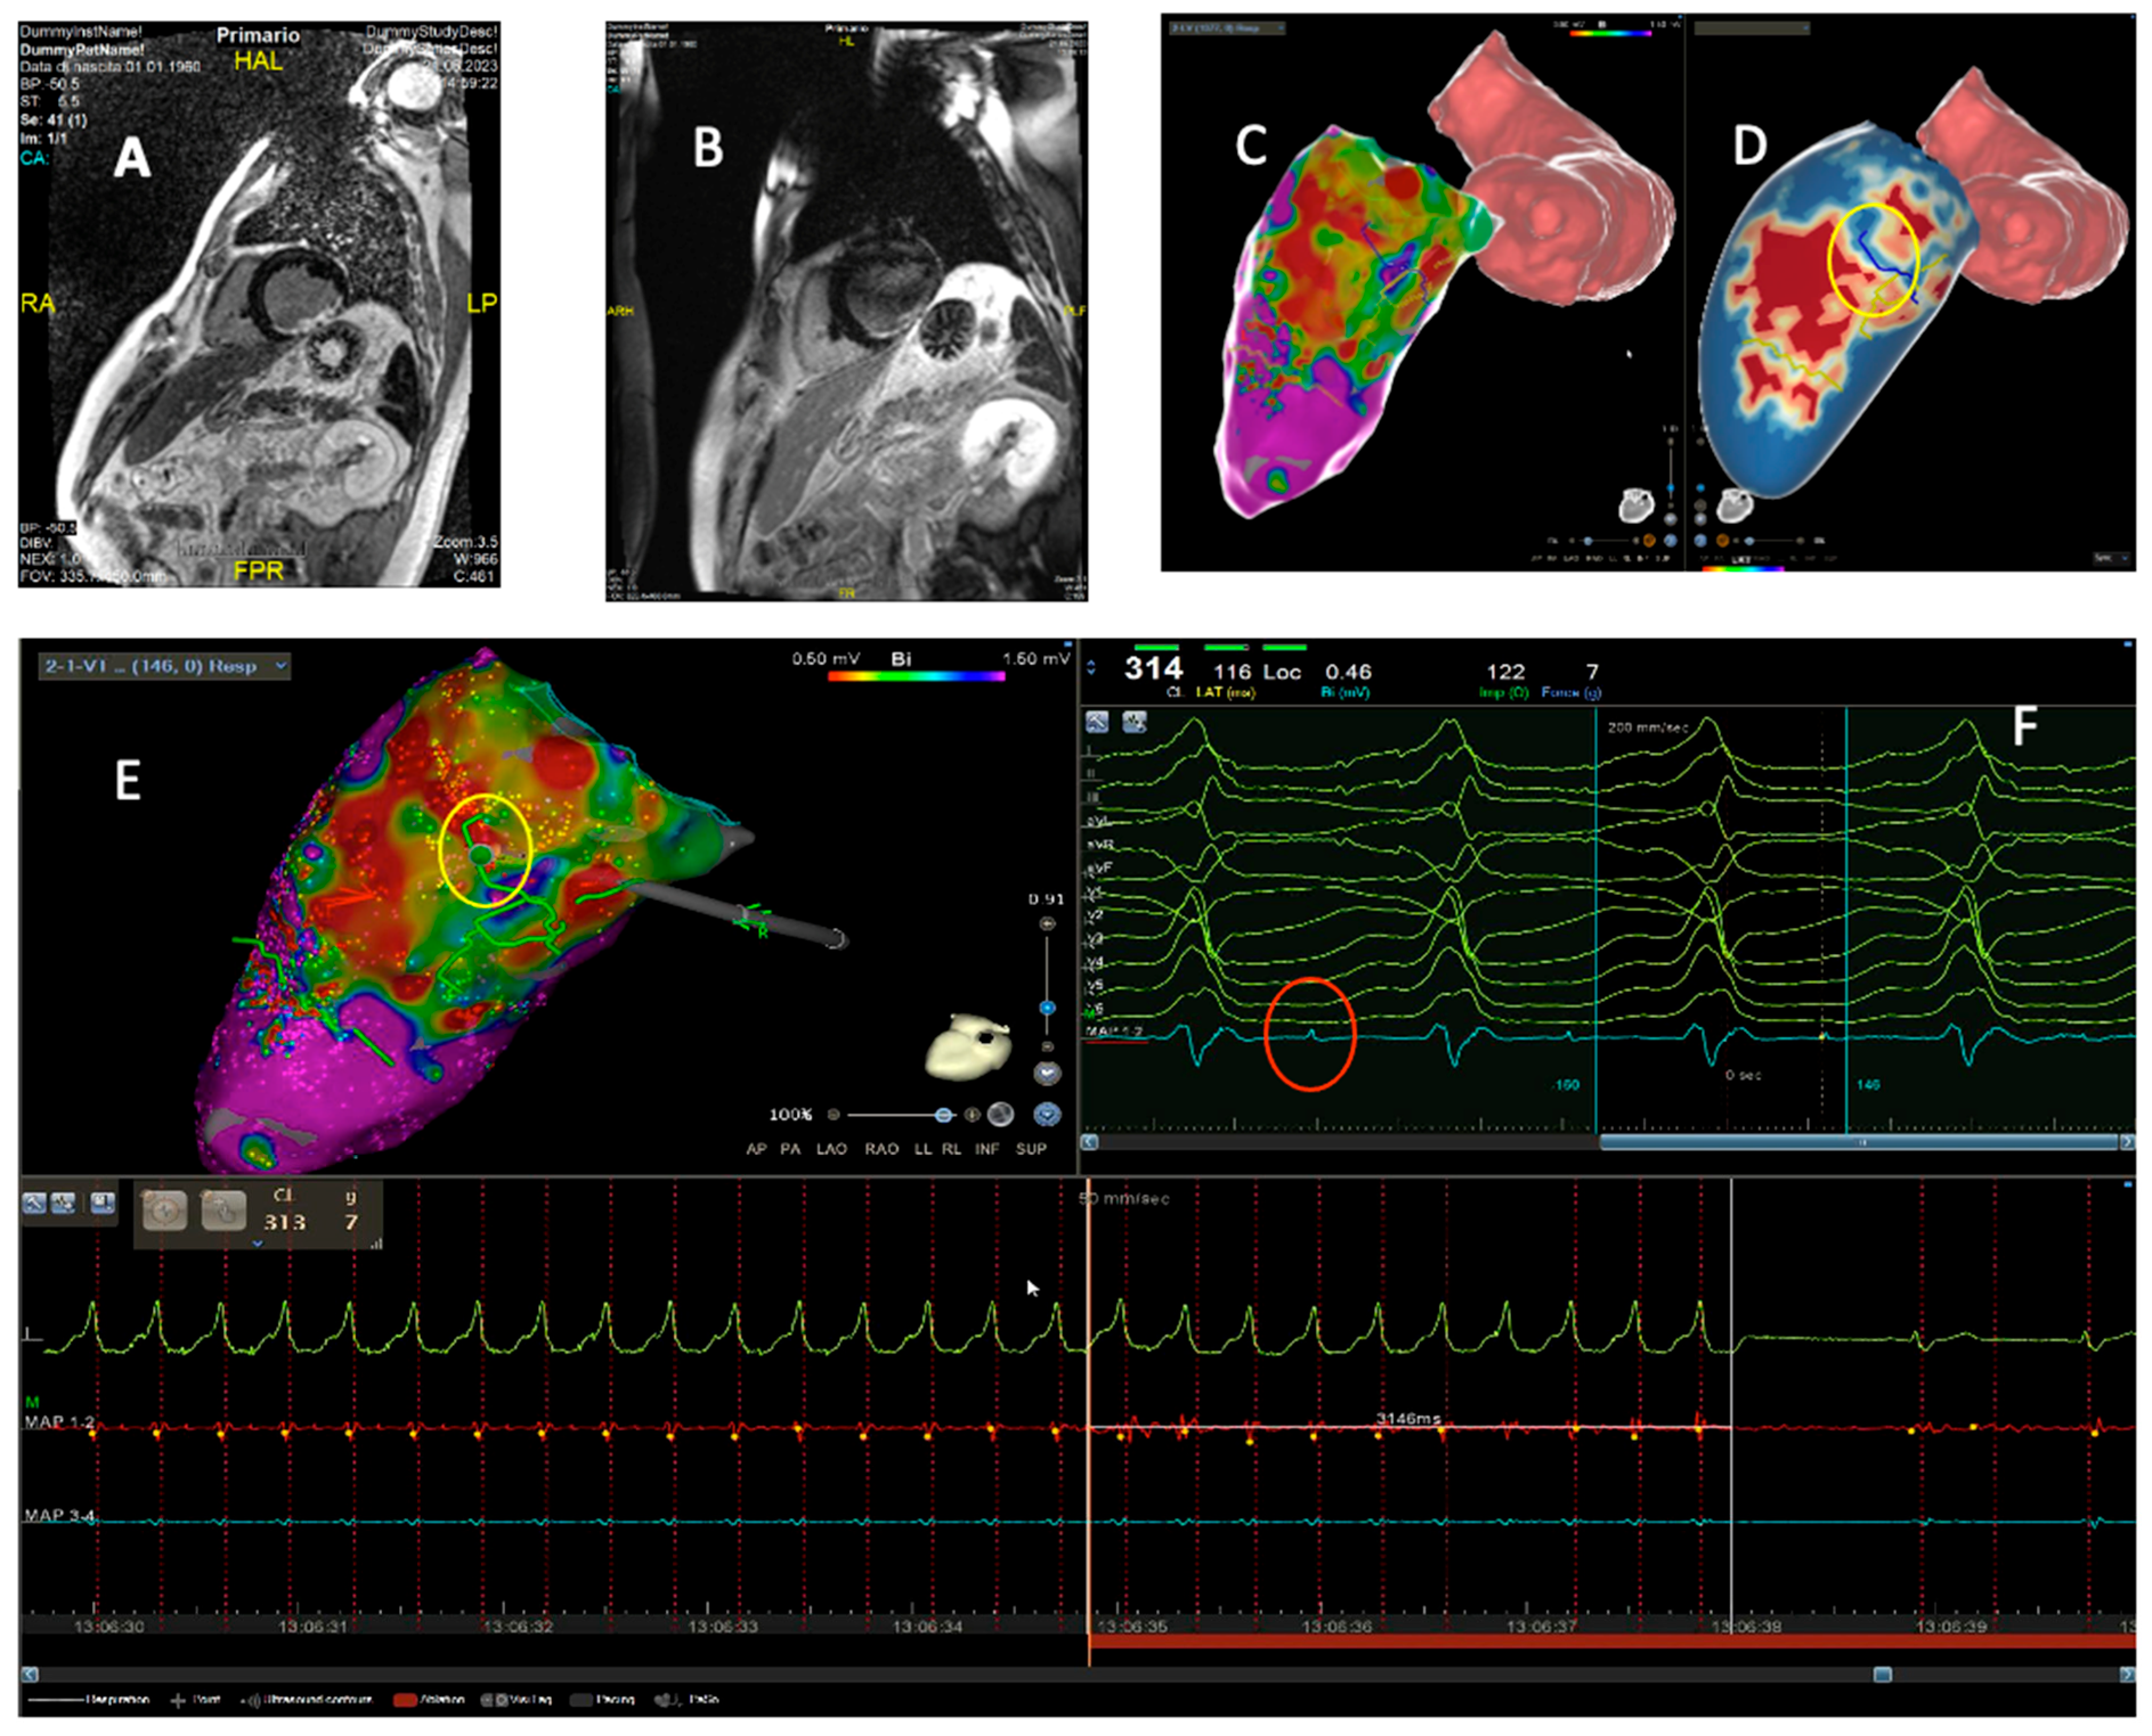

4. Intraprocedural Imaging: Focus on CT and CMR

- Andreu, D.; Penela, D.; Acosta, J.; Fernández-Armenta, J.; Perea, R.J.; Soto-Iglesias, D.; et al. Cardiac magnetic resonance–aided scar dechanneling: Influence on acute and long-term outcomes. Heart Rhythm. 2017, 14, 1121–1128. [Google Scholar] [CrossRef]

- Soto-Iglesias, D.; Penela, D.; Jáuregui, B.; Acosta, J.; Fernández-Armenta, J.; Linhart, M.; et al. Cardiac Magnetic Resonance-Guided Ventricular Tachycardia Substrate Ablation. JACC Clin Electrophysiol. 2020, 6, 436–447. [Google Scholar] [CrossRef] [PubMed]